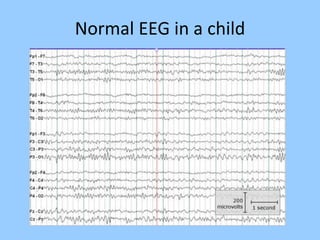

3. International standards for EEG electrode placement and recording parameters are reviewed. Characteristics of different EEG waves, amplitudes, and patterns are described.